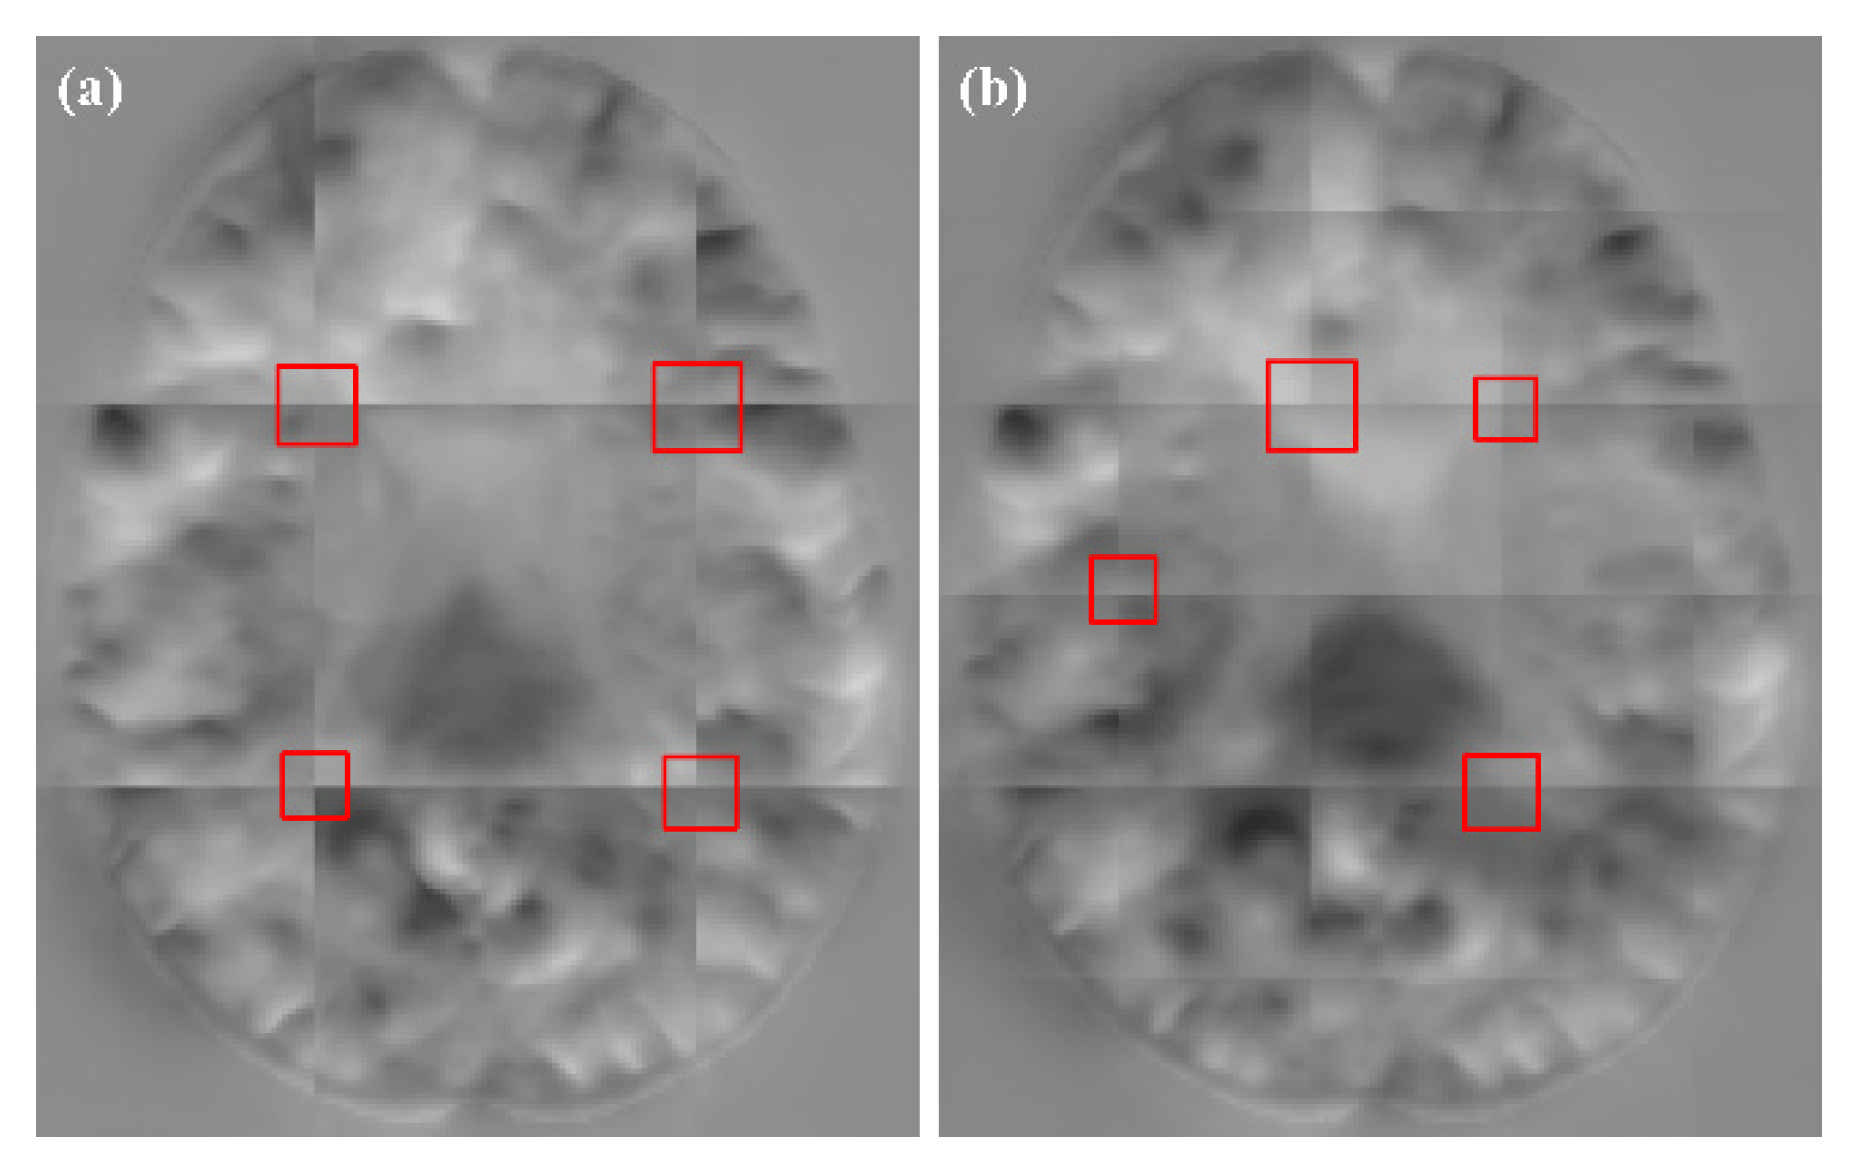

As can be seen from Table 2, our method obtained higher DSC values when compared with the other three methods. However, the values of MIScnn and AAW were lower, and the resulting DDF was smoother. In Figure 8, we show the DDFs of different fusion methods. It can be seen that the DDFs of AAW, MIScnn and patchify have obvious seam lines between patches, which indicates that the prediction of the edge region was inaccurate. Since our method considered the uncertainty of the edge, different weights were given to the center regions and the edge regions, which effectively eliminated the seams. From the enlarged red box, we can see that the DDF obtained by our method does not show grid-like artifacts. However, from the red markers, both our method and patchify retain many folding points which was mainly caused by the predicted model itself, while both the AAW and MIScnn methods changed the predicted values to some extent.

Figure 8.

The fusion results for different methods. The positions of are marked in red. From left to right: AAW method; MIScnn; patchify and our proposed.